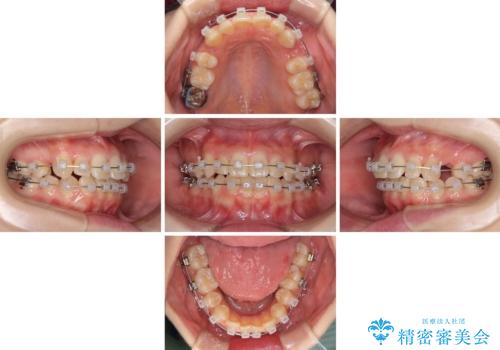

- 矯正装置

- クリアブラケット

- 2年2ヶ月

上下のバランスを取るため、上顎左右第一小臼歯2本を抜歯し、ワイヤー矯正を行うこととしました。

抜歯矯正を行ったことで、デコボコが改善されただけでなく、口元も下がったことで口が閉じやすくなりました。